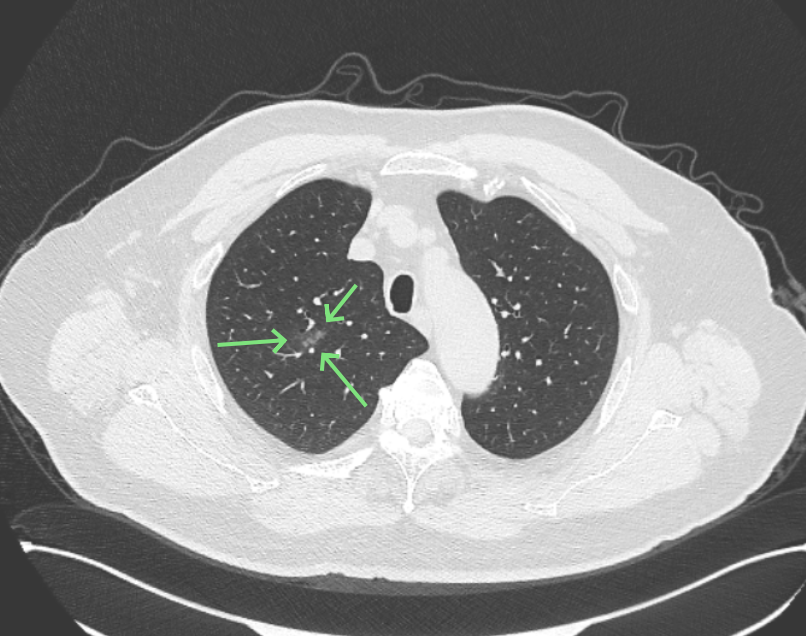

影像展示与分析:

方形的是25年的,红色的主病灶,磨玻璃密度伴少许略偏高点密度,但还说不上典型混合磨玻璃病灶,考虑原位癌或微浸润性腺癌可能性大;蓝色的轮廓与边界欠清,位置靠上叶中央,无法段切或楔切;黄色的多发均淡而纯,分布在两肺。圆形粉色的是主要的两处23年时的样子,对比说不上很明显进展。鉴于若手术得切肺叶,何况两肺他处仍的结节,年纪又74了。我倾向保守点,先6-9个月复查,等进展并风险增加再来考虑怎么办的事。意见供参考!

病灶没有确切纵隔窗可见的实性成分,但与血管关系较为密切。